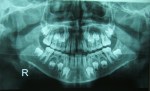

Η διάγνωση γίνεται αφού μελετηθούν¨:

1) Οι ακτινογραφίες του ασθενούς (συνήθως πανοραμική και πλάγια κεφαλομετρική ακτινογραφία)

πανοραμική ακτινογραφία